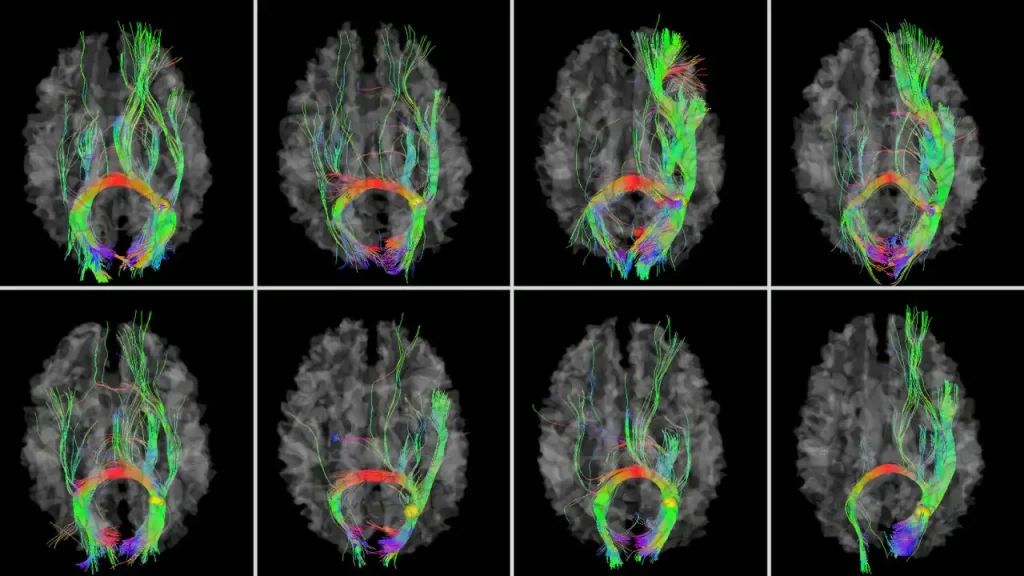

سودو اسکن یک روش پیشرفته و غیرتهاجمی برای ارزیابی فعالیتهای مغزی است که با استفاده از امواج رادیویی، تصاویر دقیقی از عملکرد مغز ارائه میدهد. این روش به ویژه در تشخیص اختلالات عصبی و روانی مانند افسردگی، اضطراب، ADHD و صرع کاربرد دارد.

در مقایسه با روشهای سنتی مانند ام آر آی و CT اسکن که عمدتاً ساختار آناتومیک مغز را بررسی میکنند، سودو اسکن به تحلیل عملکردی مغز میپردازد. به عبارت دیگر، در حالی که MRI و CT اسکن ( بهترین مراکز سی تی اسکن در تهران) تصاویر ساختاری از مغز ارائه میدهند، سودو اسکن فعالیتهای الکتریکی و شیمیایی مغز را مورد بررسی قرار میدهد.

۱. تجهیزات پیشرفته و بهروز

کلینیک ویستان از جدیدترین دستگاههای QEEG با استانداردهای جهانی استفاده میکند. این تجهیزات دقت بالایی در ثبت فعالیتهای مغزی دارند و تحلیل دادهها را با جزئیات کامل ممکن میسازند. دقت تجهیزات باعث میشود نتایج تست قابل اعتماد باشد و بیماران با اطمینان بیشتری نسبت به درمانهای بعدی تصمیمگیری کنند.